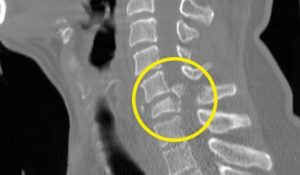

Kết quả chụp X quang cho thấy, anh bị gãy cột sống cổ di lệch thứ phát sau tai nạn chèn vào tuỷ gây liệt chân tay. Anh An phải mổ và điều trị phục hồi liệt lâu dài.

ntừ trên cao xuống là tai nạn rất nguy hiểm, rất dễ gẫy cột sống. Gãy cột sống đe doạ trực tiếp đến tính mạng. Đồng thời để lại di chứng rất nặng như: liệt tứ chi, mất hoàn toàn cảm giác. Khó hồi phục được kể cả khi đã phẫu thuật.